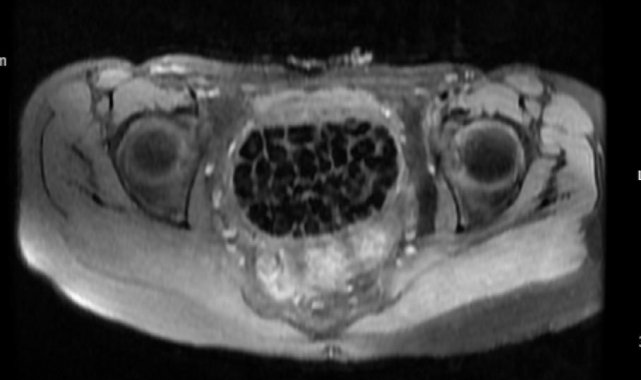

Hastasının durumuna yönelik konuşan Üroloji Uzmanı Doç. Dr. Erkan Erkan, "Hastamızın 2004 yılında doğduğunu ardından doğar doğmaz ekstrofi vezika dediğimiz 50 binde bir görülen bir anomaliden dolayı art arda ameliyatlar geçirdiğini öğrendik. 10 yaşında yine bir ameliyat geçirmişti, gerekli görüntüleme ve tetkiklerimizi yaptırdık. Normalde mesanesinin olması gereken yerin hemen arka kısmında taşlarla dolu bir kese olduğunu gördük, bunun üzerine ek görüntülemeler; MR çektirdik. Hastamız çelişkili açıklamalar almıştı, kendi radyolojik kliniğimiz ve edindiğimiz konsültasyonlarda taşların mesanede değil vajinal boşlukta oluştuğunu düşündük, bir planlama yaptık. Kadın doğum hocamızın da çabasıyla taşları tamamen temizledik ardından ileride normal bir hayat sürmesi bakımından oraya plastik cerrahi yaptık. 287 adet taş çıkardık, pratikte gerçekten görünce çok şaşırdık çünkü bu aynı zamanda literatürde çok nadir görülen bir olay. Biz ameliyata hazırlanırken de teorik olarak biraz araştırdık. Literatürde gördüğümüz kadarıyla buna benzer bu tanıma uyan bir vaka vardı. Literatürde sanırım yayınlanmış 2'nci vaka olacak. Farkındalık çok önemli, bilinçli bir hastamız vardı. Doğumsal anomaliyle doğan çocuklarımızda ileride bunlara bağlı bazı sıkıntılar çıkabileceğinin öngörülmesi lazım. İlgili tedavilerini alsalar bile düzenli takiplere gelmeleri gerekiyor. İleride eğer dikkat etmezse ki zannetmiyorum, tekrarlayabilir. Bu rahatsızlık ekstrofi vezikal epispadias durumu çok nadir bir durum" dedi.

Genç kızın uzun süredir devam eden karın ağrısı olduğunu söyleyerek sözlerine başlayan Jinekolojik Onkoloji Uzmanı Op. Dr. Emin Erhan Dönmez, "Mesane taşları olduğu düşünülerek daha büyük bir hastaneye refere edilmiş. Aramızda mini bir konsey yaparak muayene ettik. Vajen bir hazne görevi görerek orada durağan bir idrar, uzun süre beklediği için idrar içindeki minerallerde çökerek taşlar oluşmuş. Mesanedeki idrarın vajene akmış olabileceği ve vajende göllenen idrar nedeniyle taşların burada oluşacağını düşündük, ameliyatımızı planladık. Ameliyata tanı amaçlı girmiştik, sistoskopi (Mesane gibi idrar yollarını kapsayan kısımlardaki rahatsızlıkların teşhis ve tedavisinde kullanılan endoskopik bir yöntem) dediğimiz ameliyatı Erkan Hocam ile birlikte gerçekleştirdik. Önce mesaneyi bir görüntüledik, mesane tabanına yaklaşık 2-3 cm'lik bir alandan vajene fistülize olduğunu gördük. Mesaneden vajene geçtiğimiz esnada tüm vajenin taşlarla dolu olduğunu gördük. Tanı amacıyla girdiğimiz ameliyatta her şey de olağan gittiği için tedaviye geçtik. Taşların çıkabileceği kadar bir genişlik sağladık. Daha sonra yaklaşık en büyüğü 2,5 cm boyutlarında olan, irili ufaklı 287 tane taşı ameliyat esnasında çıkarmış olduk. Taşların tekrarlamaması için idrarın göllenmemesi, en azından dışarıya rahatça boşalabilmesi için vajinal rekonstrüksiyonu sağladık. Ameliyatta da herhangi bir problem yaşamadık. Literatürü Erkan Hocam ile birlikte değerlendirmiştik. Primer olarak vajende birikmiş olan bu kadar çok sayıda taşla ilgili bir makale görmedik, rastlamadık" dedi.